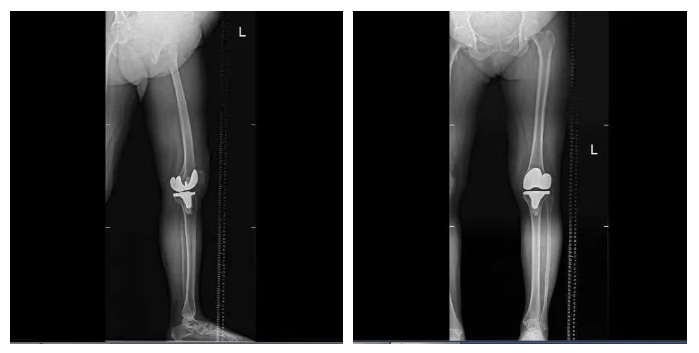

手術全程操作流暢高效,通過術后測量顯示,實際截骨量、術后下肢力線與術前規(guī)劃完全一致,真正實現(xiàn)了高效和精準。此外,鴻鵠?的自動定位截骨功能,避免了傳統(tǒng)手術中采用髓內定位工具可能會對患者髓腔造成一定損傷等問題,很大程度減少了軟組織和骨組織的損傷,患者出血少、創(chuàng)傷小,術后膝關節(jié)功能的康復更快。據(jù)悉,患者術后恢復良好,第二天即可進行早期功能鍛煉。

▲患者術后平片